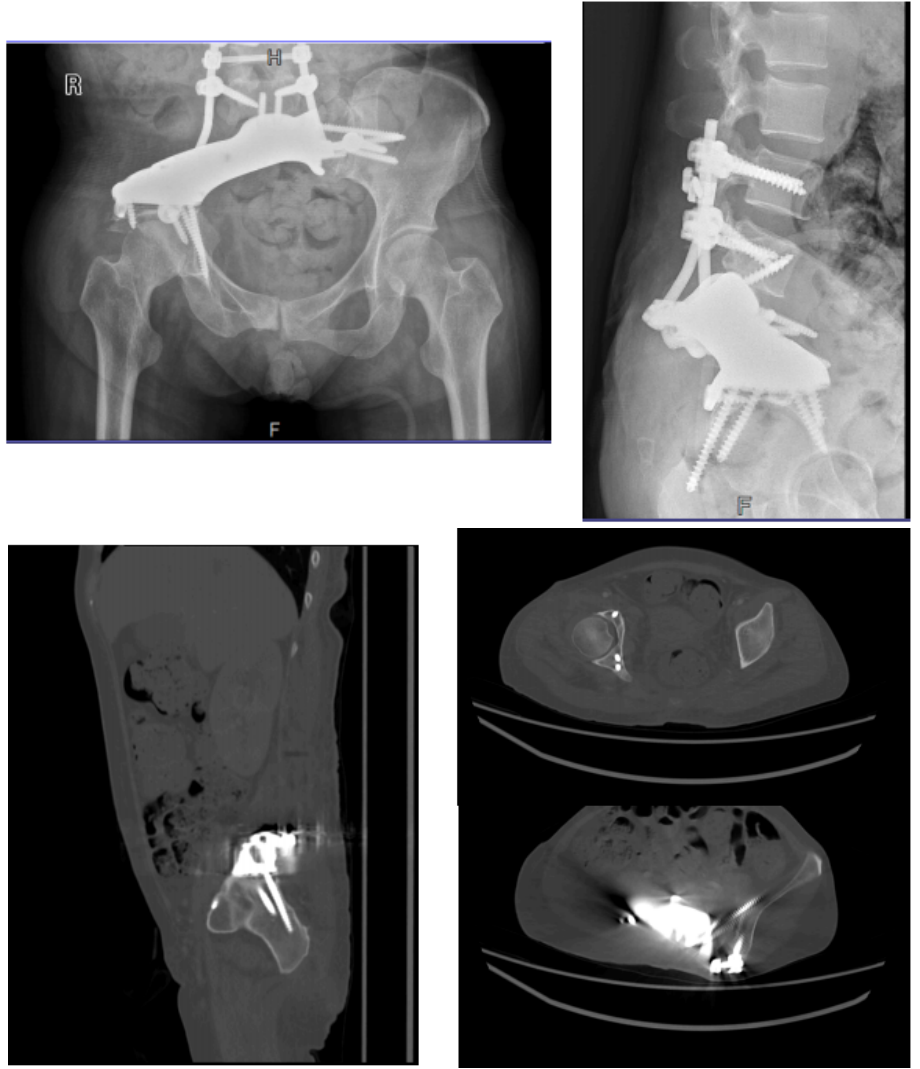

手术由骨肿瘤团队统筹,麻醉科、手术室、输血科等多科室协作完成。术中团队实施肿瘤根治性切除,并完成骨盆功能重建。术后影像学显示,定制型半骨盆位置良好,假体-骨界面有效接触。

图3术后复查影像学。定制型半骨盆位置良好,假体-骨界面有效接触。